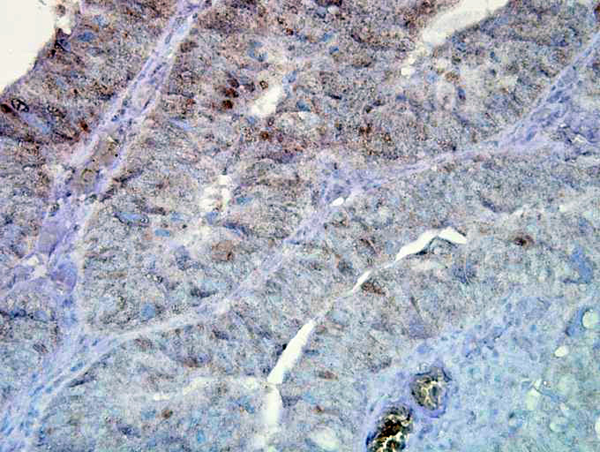

IHC (Immunohistochemistry)

(Immunohistochemistry analysis using Mouse Anti-Hsp90 Monoclonal Antibody, Clone D7alpha. Tissue: colon carcinoma. Species: Human. Fixation: Formalin. Primary Antibody: Mouse Anti-Hsp90 Monoclonal Antibody at 1:100000 for 12 hours at 4 degree C. Secondary Antibody: Biotin Goat Anti-Mouse at 1:2000 for 1 hour at RT. Counterstain: Mayer Hematoxylin (purple/blue) nuclear stain at 200 ul for 2 minutes at RT. Magnification: 40x.)